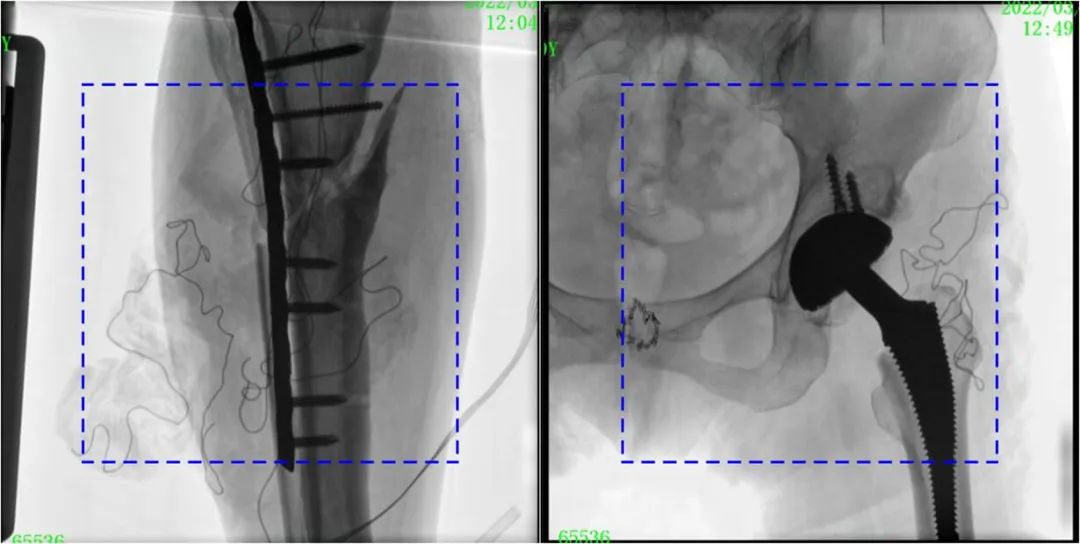

在進行髓內釘內固定術時,醫生需要同時觀察到入釘點和骨折部位的情況,普愛醫療大平板一體式C形臂采用30CM×30CM的平板探測器,能夠呈現更廣闊的成像面積,滿足大部分長骨髓內釘內固定術的攝片需求。

PLX119C臨床圖像與傳統圖像對比

注:藍色虛線內為傳統21CM×21CM平板的成像區域。